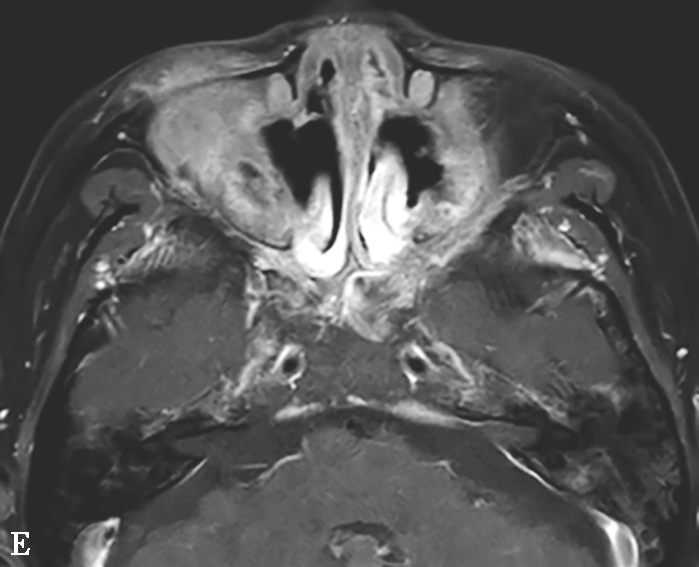

图1-3-25 慢性侵袭性真菌性鼻窦炎

A、B.横断面CT及冠状面CT骨窗,示右侧蝶窦可见软组织影充填,蝶窦侧壁欠光整,骨皮质略模糊;C.横断面T 2 WI,示右侧蝶窦病变呈混杂等略低信号,右侧海绵窦受累增厚;D.横断面T 1 WI,示病变呈略高信号;E.横断面T 1 WI+FS+C,示蝶窦腔病变大部分无强化,可见不规则索条状明显强化影,窦腔边缘黏膜增厚强化,右侧海绵窦受累增厚强化,斜坡及Meckel腔脑膜增厚强化;F.冠状面T 1 WI+FS+C,示蝶窦病变破坏鞍底骨质,累及鞍上及右侧海绵窦,垂体受累轻到中度不均匀强化,蝶窦黏膜弥漫性增厚强化